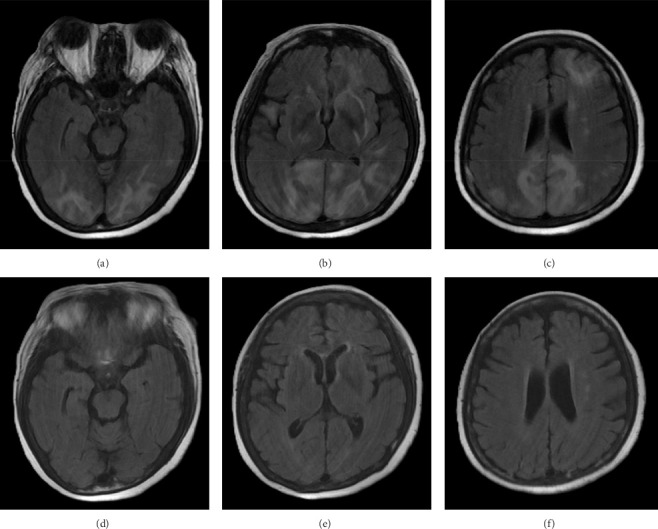

Introduction: Posterior reversible encephalopathy syndrome (PRES) is a neurological emergency typically associated with hypertension or drug toxicity. Although mirtazapine is not a classical serotonergic agent, overdose may induce serotonin syndrome, which can contribute to PRES. Case Presentation: A 50-year-old woman presented with seizures, impaired consciousness, and autonomic instability following ingestion of > 300 mg mirtazapine. Magnetic resonance image (MRI) revealed vasogenic edema in the parieto-occipital and frontal lobes. Her clinical features fulfilled the Hunter criteria for serotonin syndrome. Treatment with cyproheptadine led to full clinical and radiological recovery. Discussion: Serotonin syndrome may disrupt cerebral autoregulation and impair endothelial integrity, contributing to PRES. Although rare, similar cases have been reported with other serotonergic agents. This is the first reported case of mirtazapine overdose resulting in serotonin syndrome-associated PRES. Conclusion: Clinicians should recognize that mirtazapine overdose can cause serotonin syndrome and secondary PRES. Early identification and serotonin antagonism are crucial for recovery and prevention of sequelae.